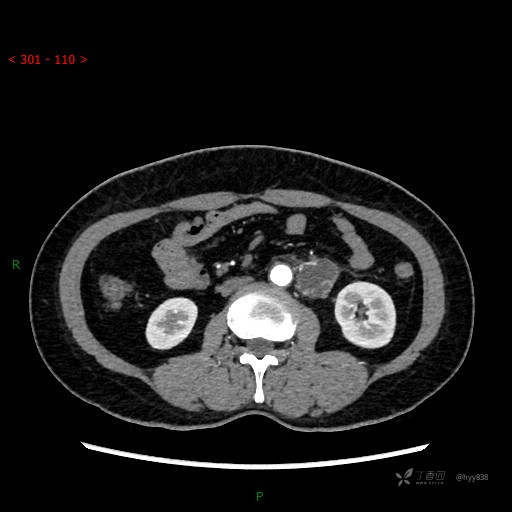

增强动脉期